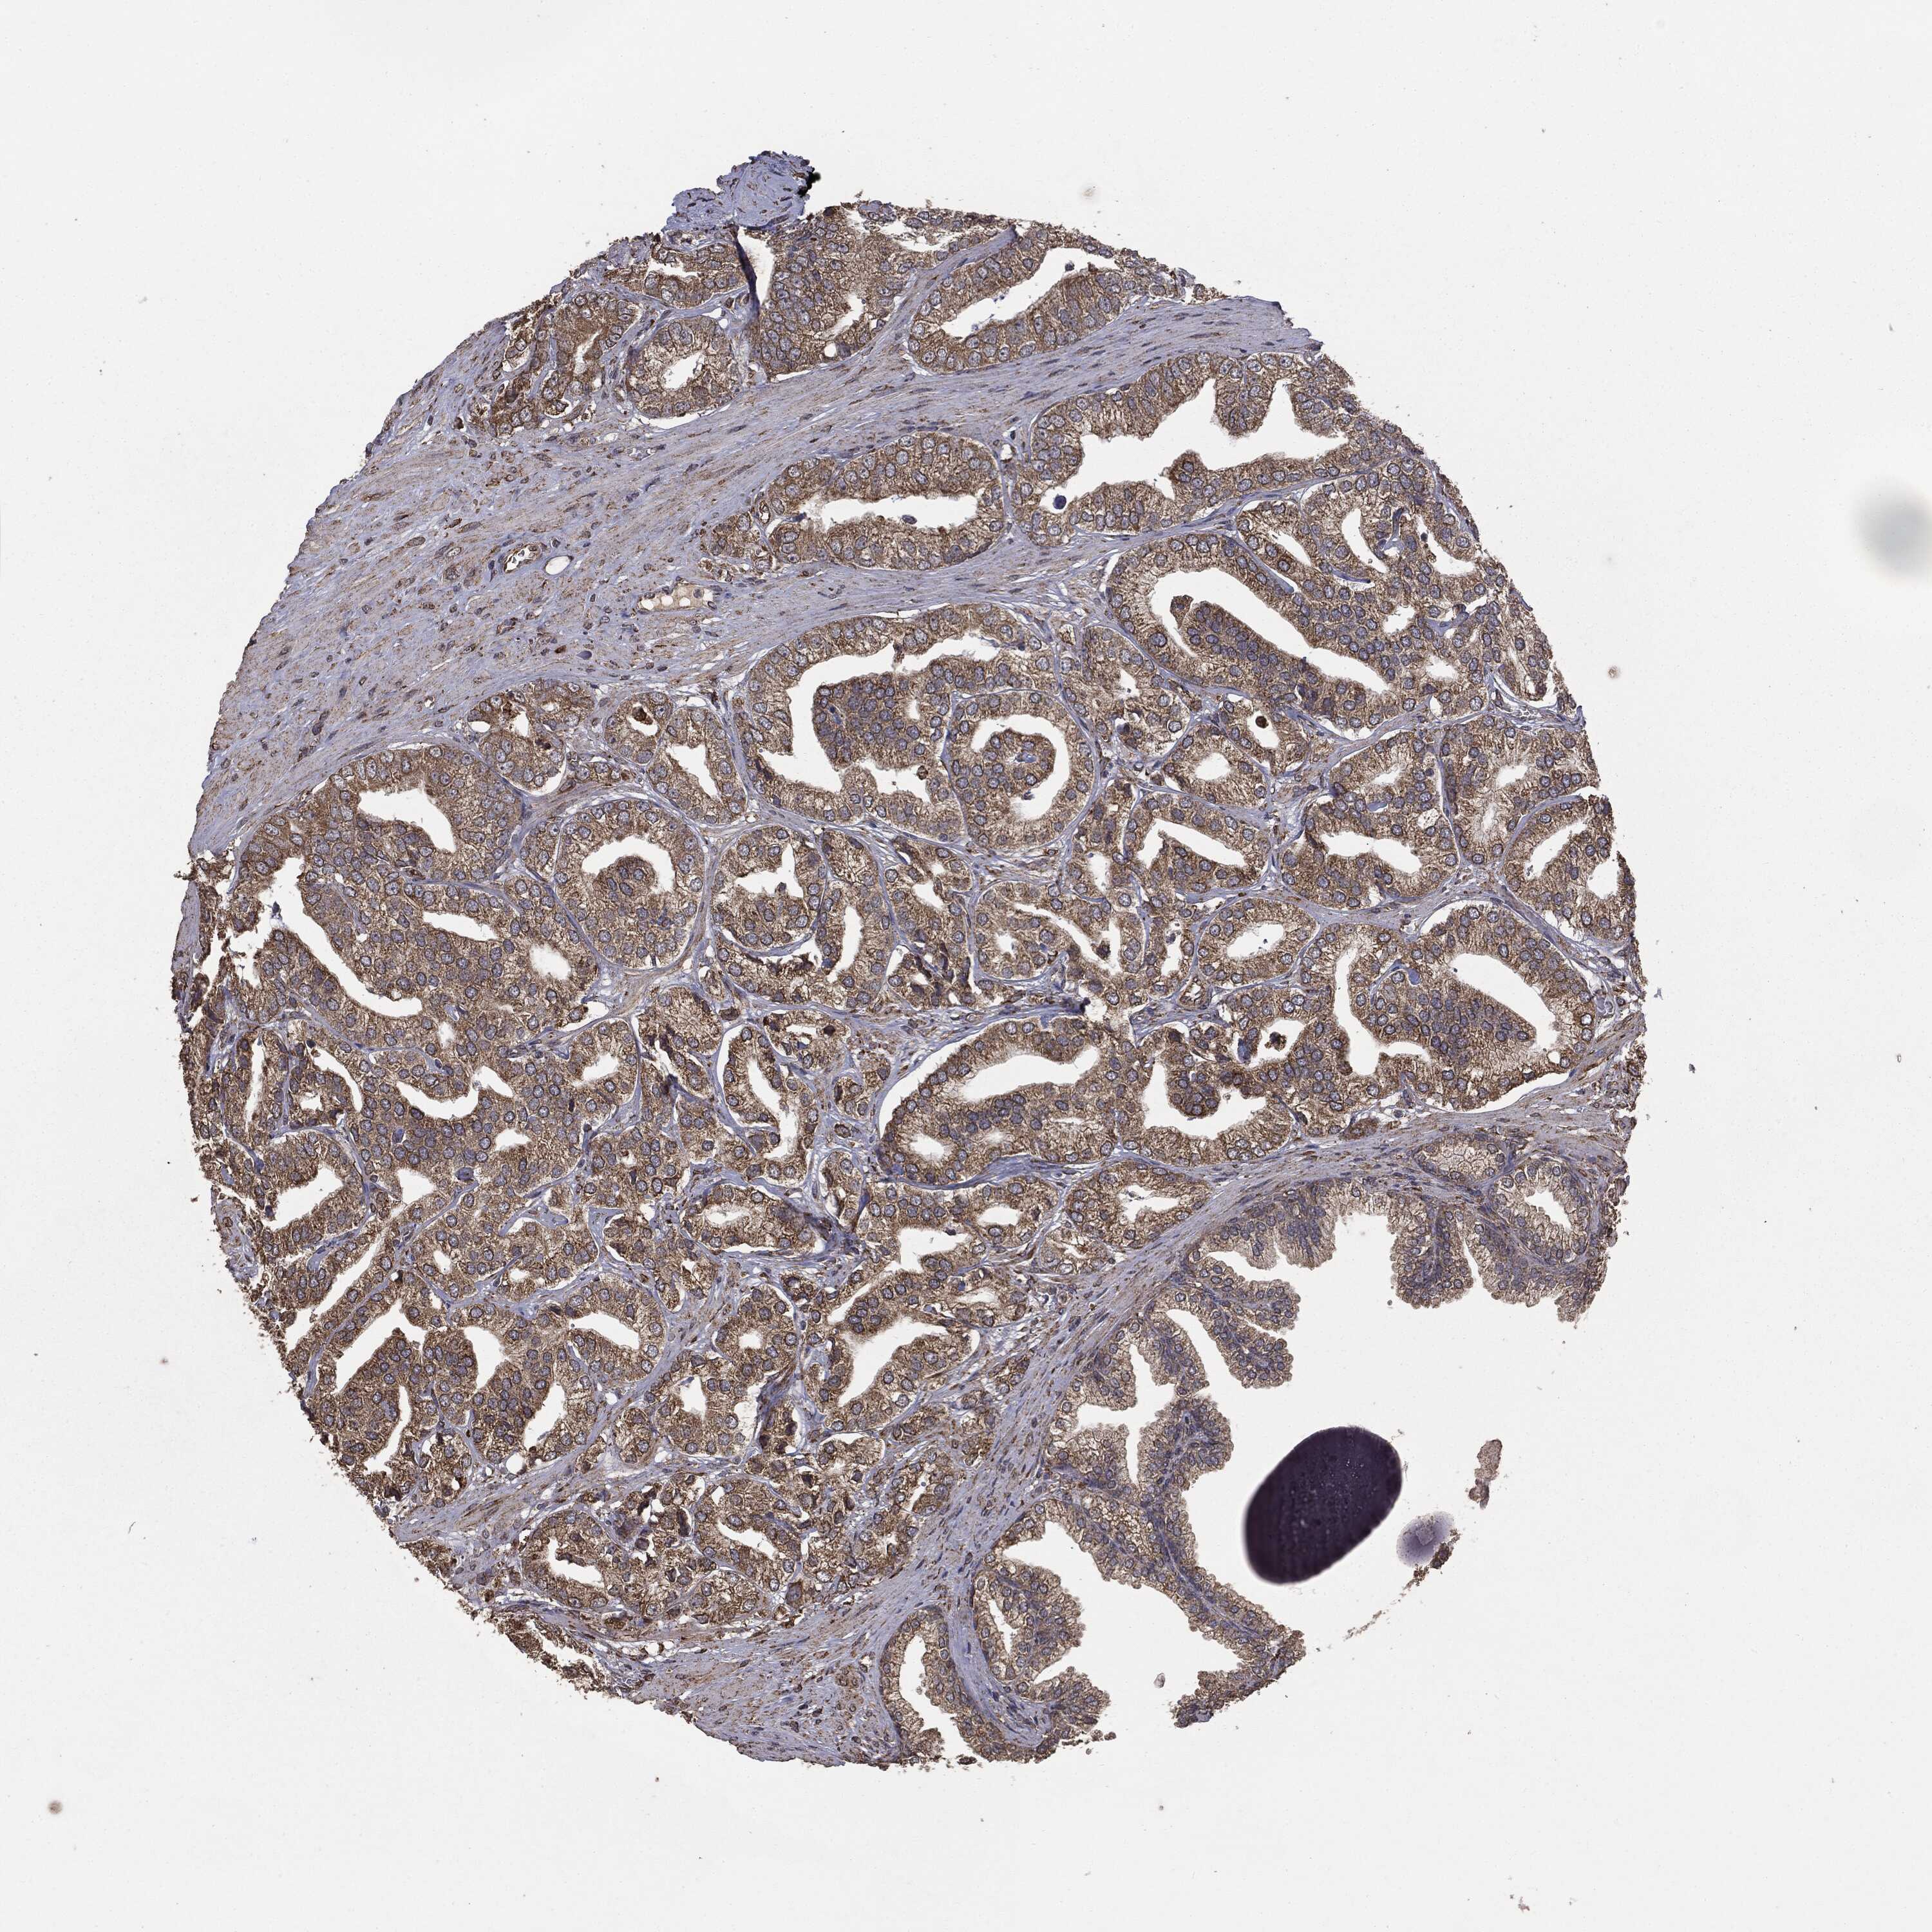

PROSTATE CANCER - Protein expressioni

A mouse-over function shows sample information and annotation data. Click on an image to view it in a full screen mode. Samples can be filtered based on level of antibody staining by selecting one or several of the following categories: high, medium, low and not detected. The assay and annotation is described here.

Note that samples used for immunohistochemistry by the Human Protein Atlas do not correspond to samples in the TCGA dataset.

Antibody stainingi

Antibody staining in the annotated cell types in the current human tissue is reported as not detected, low, medium, or high, based on conventional immunohistochemistry profiling in selected tissues. This score is based on the combination of the staining intensity and fraction of stained cells.

Each image is clickable and will lead to virtual microscopy that enables deeper exploration of all samples and also displays staining intensity scores, fraction scores and subcellular localization as well as patient and tissue information for each sample.

CAB069425

CAB080053

CAB080065

CAB080070

CAB080081

CAB080095

CAB080097

Staining

High

Medium

Low

Not detected

Intensity

Strong

Moderate

Weak

Negative

Quantity

>75%

75%-25%

<25%

None

Location

Nuclear

Cytoplasmic/membranous

Cytoplasmic/membranous,nuclear

Adenocarcinoma, High grade

Adenocarcinoma, NOS

Adenocarcinoma, Low grade